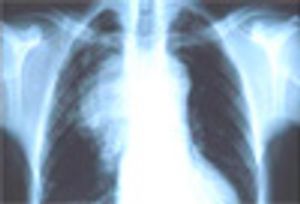

A 71-year-old man was admitted to the MICU for weaning from mechanical ventilation. The history revealed a global decline over the previous 3 to 4 weeks predominated by cognitive impairment, mood swings, somnolence, and limb weakness. No respiratory symptoms were noted.